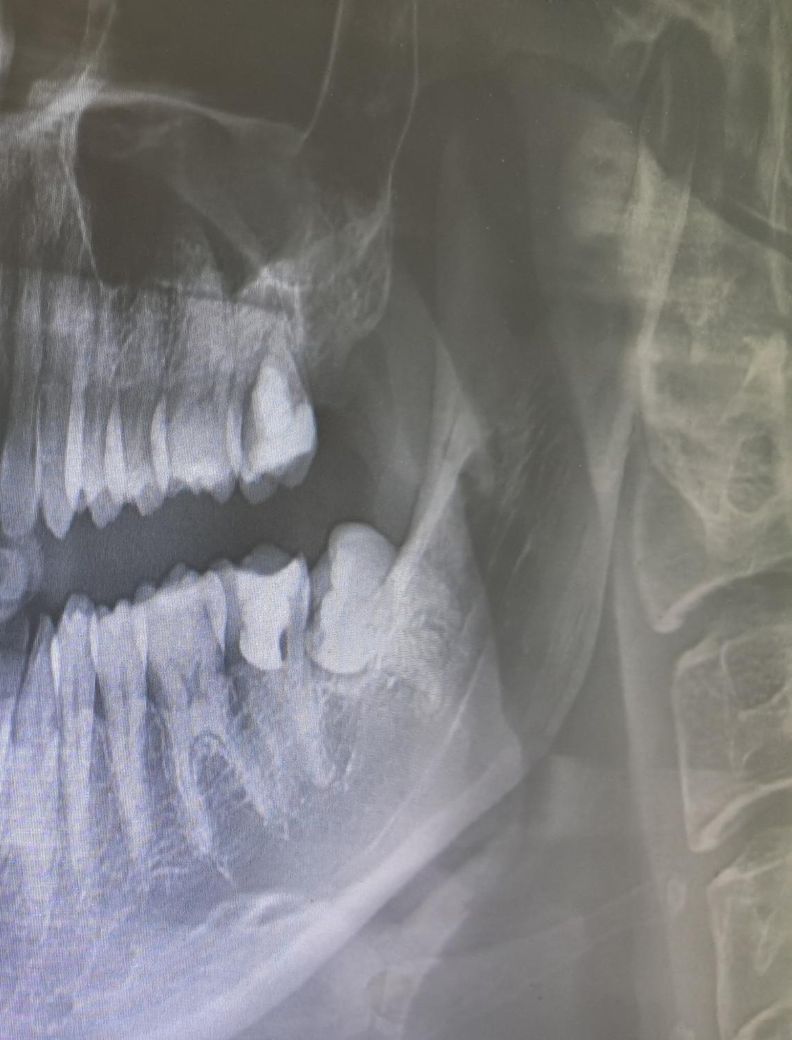

왼쪽 위의 어금니도 재신경치료를 받아야 할까요??

현재 왼쪽 아래 사랑니를 빼고 왼쪽 아래 어금니는 재신경치료 중에 있습니다.

다만 담당 주치의 분께서 왼쪽 위에 마지막 어금니도 재신경치료가 필요하다고 하는데 혹시 이쪽 치아도 치룐를 받아야 할까요??

신경치료가 뿌리끝에까지 되어있지는 않은 상태는 맞습니다. 하지만 특별한 증상이 없고 병소가 없다면 굳이 치료를 할 필요는 없을것으로 생각됩니다.

엄밀히 말하면 재신경치료 아닙니다. 지금 되어있는건 신경치료가 아니고 치수절단술로 부분적으로 신경치료를 해둔 겁니다. 증상이 생기면 완전 치수절제술 (완전 신경치료)를 해줍니다 증상 없두면 냅둡니다. 증상 없는데 건드릴 이유가 없습니다. 다만, 왼쪽 위 어금니도 적절한 차단과 밀폐를 위해 크라운은 씌워줄 필요가 있습니다.